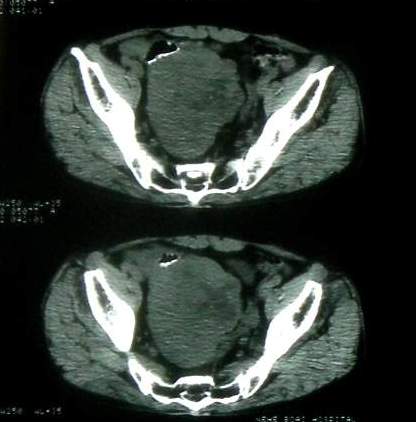

男 60岁,下腹部肿块半年余

前列腺肥大,密度不均。伴盆腔实性肿块。考虑前列腺癌伴盆腔转移。建议增强扫描。

盆腔恶性占位,间质瘤可能性大

乙状结肠间质瘤

病理结果:肠系膜肉瘤

病灶形态不规则,偏心性裂隙样坏死,支持恶性病变。来源不好定。感谢反馈结果--肠系膜肉瘤。